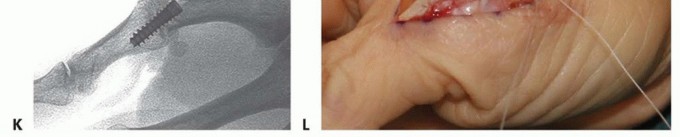

CANNULATED HEADLESS COMPRESSION SCREW FIXATION

TECH FIG 3 • (continued) I. Its position is checked with fluoroscopy. J. After the proper implant length is measured and the leading cortex overdrilled, the screw is inserted over the guidewire. K. Confirm correct final positioning with fluoroscopy. L. The joint capsule is closed and the extensor mechanism reapproximated. Reconfirm correct alignment in all planes, paying particular attention to rotation. Confirm satisfactory hardware positioning (TECH FIG 3K).Morselized bone graft can be harvested from the resected metacarpal head and packed in and around the arthrodesis site if needed.Close the joint capsule with absorbable suture to minimize extensor tendon adhesions.Approximate the extensor tendon interval with interrupted, inverted permanent suture and close the wound in a routine fashion (TECH FIG 3L).Place a forearm-based thumb spica splint.